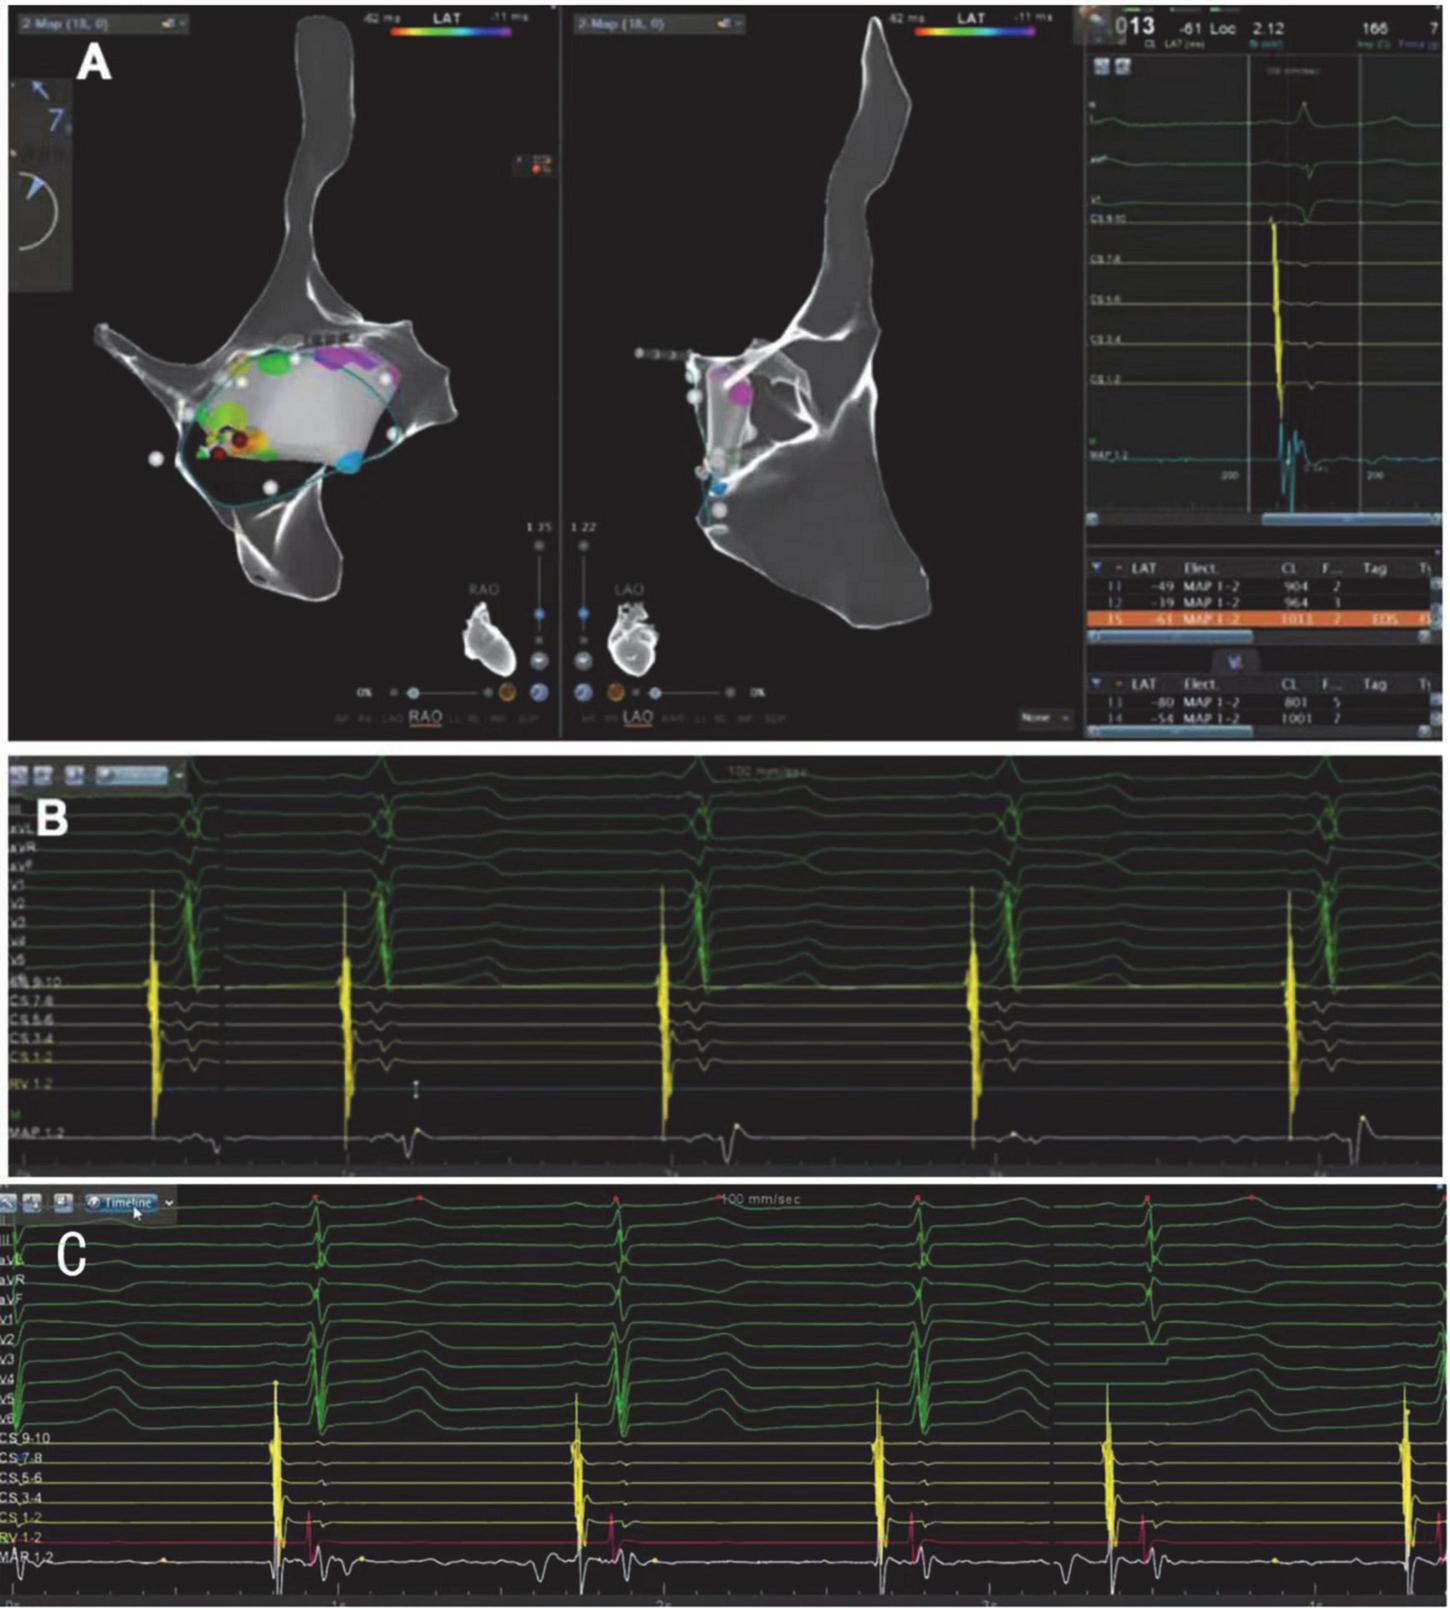

This procedure was performed under standard local anesthesia and guided by CARTO electroanatomical three-dimensional (3D) mapping system. A steerable Decapolar catheter (XTTM, Bard Electrophysiology, Lowell, MA, USA) and 4 polar catheters (AVAIL, Electrophysiology Cather, Biosense Webster, USA) were positioned in the coronary sinus (CS) through the right femoral vein. An 8.5-Fr long sheath (SL1, St. Jude Medical, MN, USA) was advanced into the right atrium through the right femoral vein, and a Thermocool Smart touch catheter was introduced to the region of His-bundle from SL1 (Figure 3). Supraventricular tachycardia was induced with the frequency of 180 beats per minute by ventricular S1S1, and A was reset by right ventricular apex entrainments and RS2 stimuli. The patient was diagnosed with dextrocardia with a posteroseptal tricuspid annulus accessory pathway by the intracardiac EGM (Figures 4A,B). After ablation at 43°C and 30W for 5 s, the accessory pathway was blocked and continued to ablate for 240 s. Retrograde Wenckebach conduction was stimulated by ventricular S1S1 for 400 ms, decreased conduction was stimulated by coronary sinus S1S1 stimulation, and Wenckebach conduction was found for 300 ms. No ventricular conduction with atria stimulated by S1S2 of 450/300 ms, indicating that the procedure was successful. Delta wave disappeared on intracardiac and surface EGM (Figure 4C).

FIGURE 4

(A) CARTO electroanatomical 3-dimensional(3D) mapping system showing the right atrium is a mirror image of a normal heart in the right-anterior oblique view(RAO)and the left-anterior oblique view (LAO). (B) ECG (before RFCA) with reverse lead placement and right precordial leads V3R-V6R shows an inferoseptal tricuspid annulus accessory pathway. The prominent early V wave in 7/8 bipolar potentials of 10 polar coronary sinus electrodes also indicates the accessory pathway was in the inferoseptal nearby the coronary sinus ostium. Ventricular activation was marked by the red arrow. (C) The ECG after the radiofrequency catheter ablation shows “delta” wave disappeared, indicating that the procedure was successful.